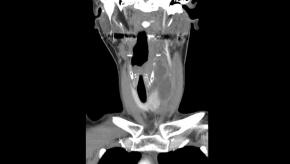

• Longitudinal image

Answer Infected 4th branchial cleft anomaly

Comments A Fourth branchial cleft anomaly is a rare congenital anomaly caused by incomplete obliteration of the fourth branchial pouch. It typically presents with recurrent left-sided neck infection or abscess, often involving the upper thyroid gland or adjacent neck spaces. The tract usually originates from the apex of the Pyriform sinus and extends inferiorly toward the thyroid gland, which explains the frequent association with recurrent suppurative thyroiditis. Recognition of this characteristic connection to the pyriform sinus is key to making the diagnosis.